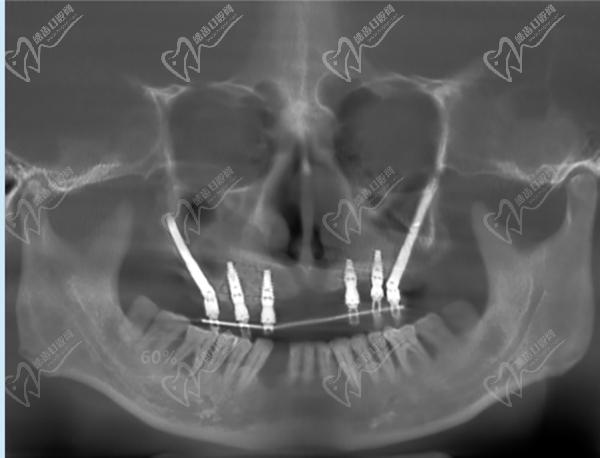

作為廣州市實力強勁的綜合性口腔醫(yī)院,暨南大學穗華口腔在種植牙領(lǐng)域名聲在外。醫(yī)院擁有一批經(jīng)驗豐 富的種植醫(yī)生,例如馮智強醫(yī)生,并擅長各種種植牙手術(shù),包括單顆種植、多顆種植、微創(chuàng)種植、數(shù)字化種植、半口/全口種植,甚至難度技術(shù)高的穿顴穿翼種植。

半口種植牙·集采種牙:21860元起

全口種植牙·集采:42720元起